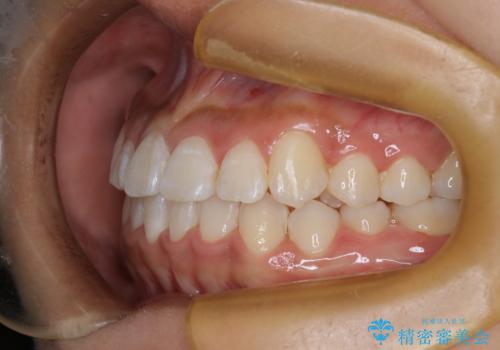

ワイヤー矯正で確実にガタつきを治したい セラミックブラケットによる治療

- 治療計画

- 前歯の叢生(がたつき)を主訴に来院された患者様です。以前マウスピース矯正をされていたそうでしたが、自身での継続が難しいことなどを理由に、ワイヤー矯正にて改めて矯正治療を希望されました。非抜歯にて治療を計画し治療を行いました。

歯の動きが良く、スムーズに治療を終了しました。一般的にワイヤー矯正はブラッシングが難しいのですが、毎回一生懸命セルフケアをされていたのが印象的です。治療においては、歯の衛生状態も一緒にチェック致します。